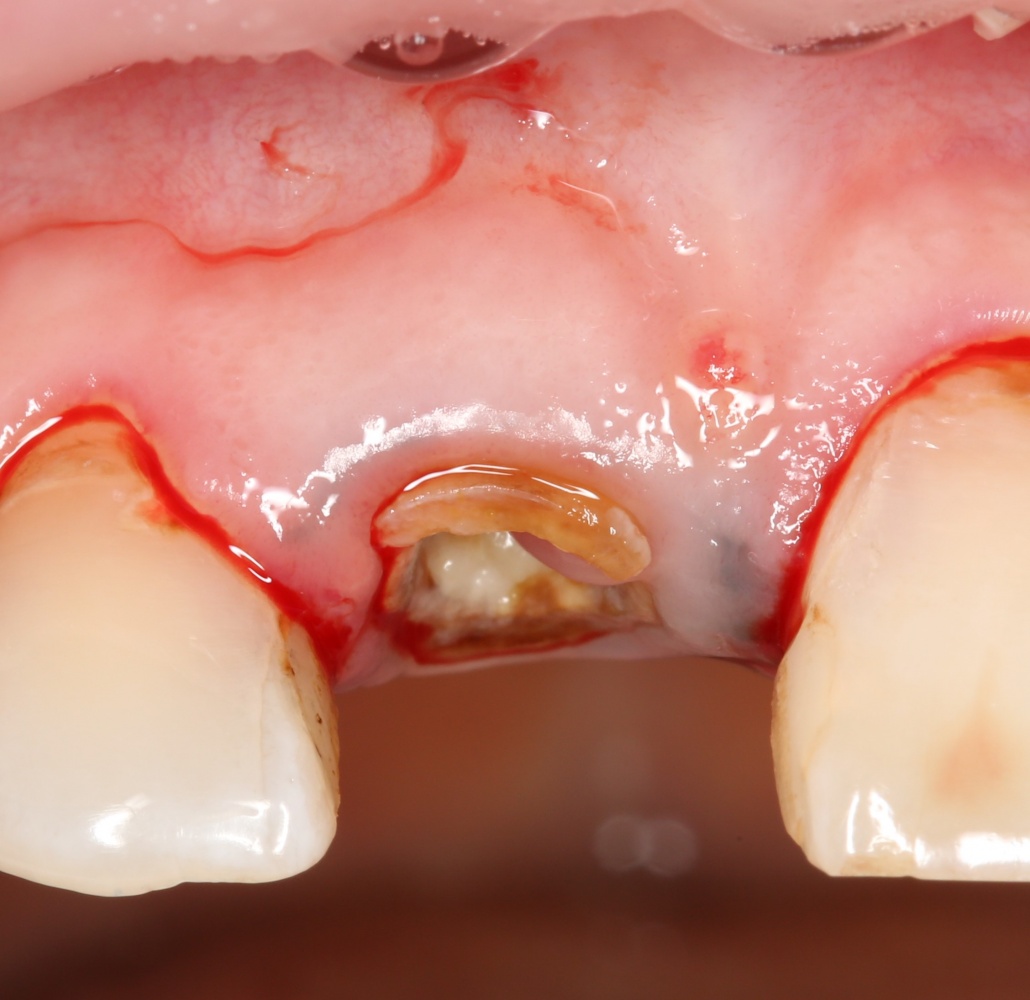

Зуб удаляется по причине периапикального воспалительного процесса, сопровождающегося активной экссудацией и образованием свищевого хода.

Конечно же, во втором варианте. При таком типе воспалительного процесс происходит лизис тканей и, как результат, вестибулярная стенка лунки довольно быстро уходит, поэтому требует поддержки. В первом варианте состояние костной ткани и слизистой оболочки таково, а само развитие воспалительного процесса сдерживается организмом, поэтому риски утраты линейных размеров альвеолярного гребня минимальны. Поэтому можно добиться удовлетворительного результата даже без аугментации лунки (на фото справа — временная коронка, установлена на следующий день после имплантации):

Во втором варианте ситуация несколько сложнее.

После удаления зуба и сопутствующей гранулемы, остается большая по размеру лунка с тонкой и поврежденной воспалительным процессом вестибулярной стенкой: